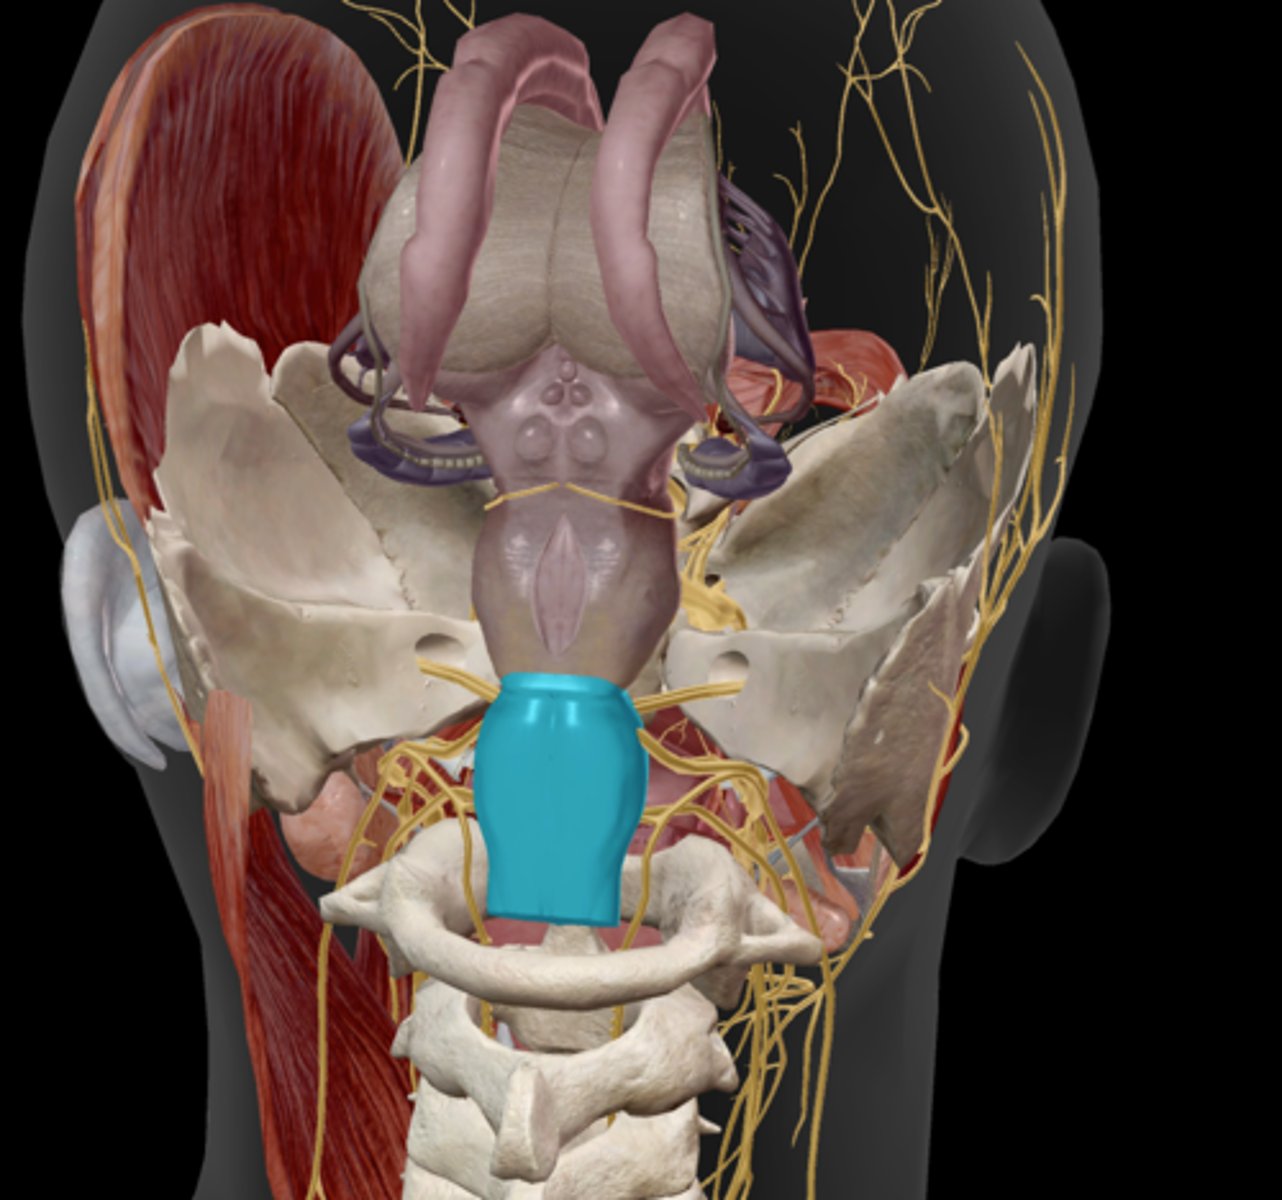

Spleen

Stomach

Esophagus

Lesser curvature

Greater curvature

Cardiac sphincter

Longitudinal muscle layer of the stomach

Oblique muscle layer of the stomach

Circular muscle layer of the stomach

Pyloric sphincter

Gallbladder

Cystic duct

Common hepatic duct

Common bile duct

Pancreas

Main pancreatic duct (duct of Wirsung)

Accessory pancreatic duct (duct of Santorini)

Liver

Hepatic artery & vein

Falciform ligament

Duodenum

Duodenal papilla

Jejunum

Ileum

Taenia coli

Superior mesenteric artery

Inferior mesenteric artery

Cecum

Appendix

Ascending colon

Transverse colon

Descending colon

Sigmoid colon

Rectum

Anal canal